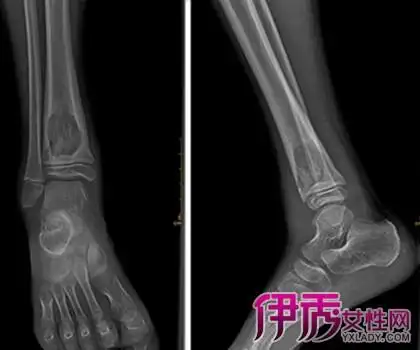

【图】脚踝滑膜炎的临床表现 为你盘点它的4种治疗方法